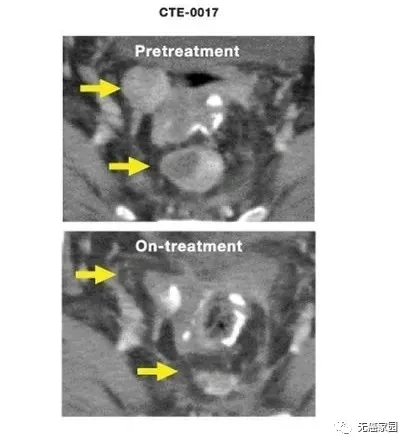

图示经过几周治疗后,患者病情得到明显控制